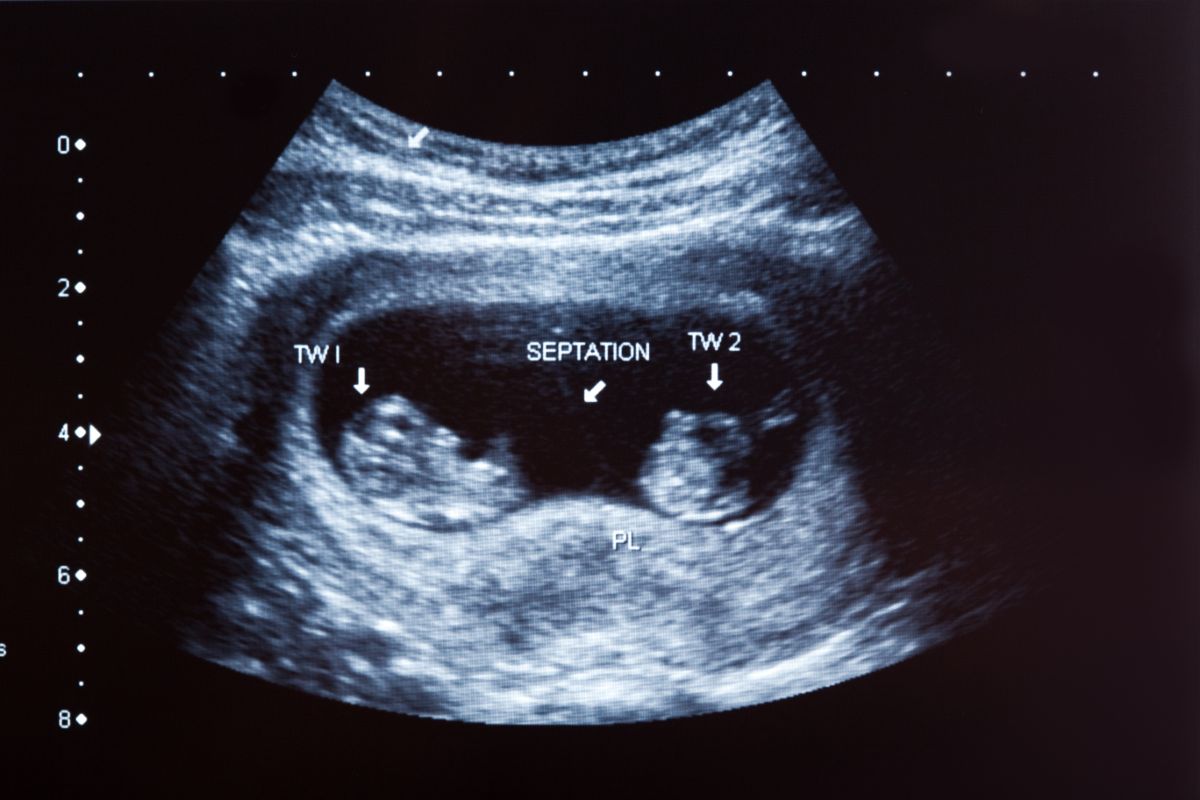

Checks for multiple pregnancies

Ultrasounds can detect your baby’s heartbeat — and show if there is more than one set of heartbeats. If your doctor detects multiple heartbeats, you will likely be having twins, triples, or more babies in this pregnancy.

Carrying more than one baby has special risks, which must be monitored by your doctors regularly. This will enable them to promptly treat you if complications like twin-to-twin transfusion occur.